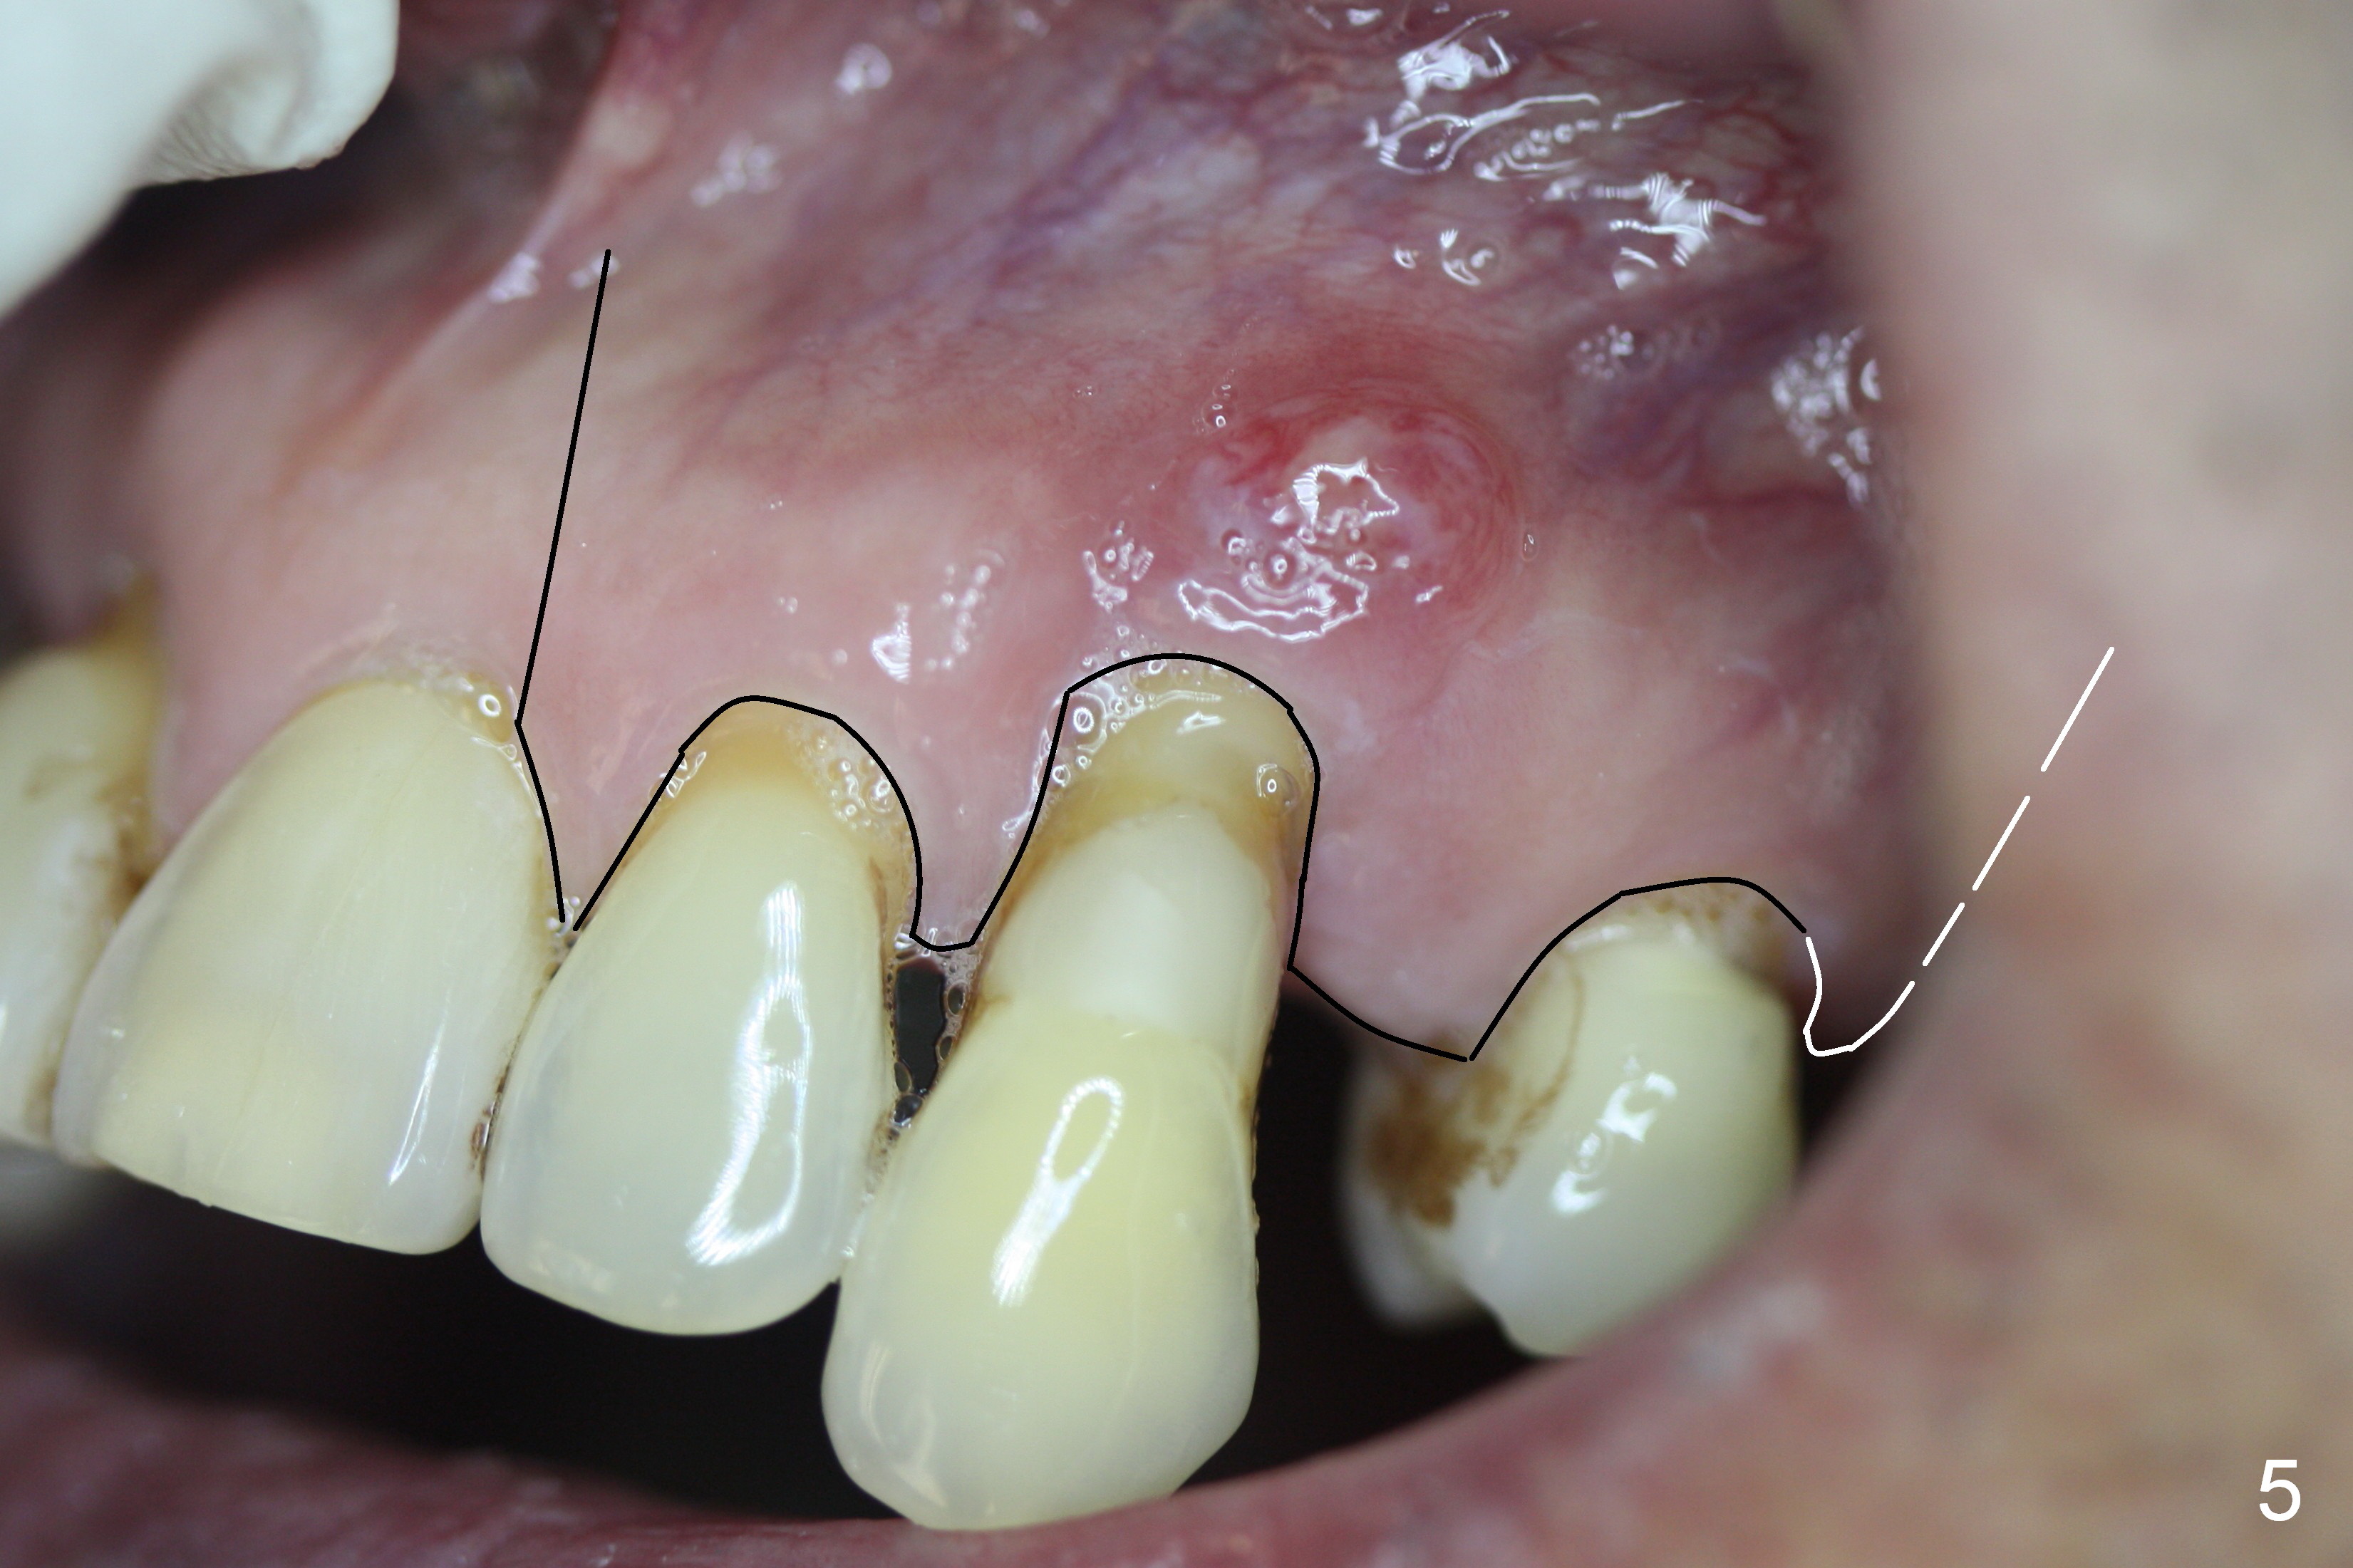

Bone defect at present should be more severe than CBCT coronal (Fig.3) and axial (Fig.4) sections indicate. After palatal placement of a 5x20 mm tissue level implant (Fig.3 green area) and an appropriate abutment, an immediate provisional is to be fabricated. A block graft is harvested from #12 edentulous region (buccal plate) to the buccal defect at the site of #11 (Fig.4 curved light blue arrow). Prepare surgical handpiece and chisels. The remaining bony defect will be filled with allograft and Osteogen (red circles). The graft site is going to be covered by Osteotape (Fig.3,4 pink curved line), while the donor site is given mixture of allograft and Osteogen and Collagen Dressing. When the soft tissue deficiency is found, connective tissue graft is to be harvested from the palate. If visibility is compromised for these steps, an incision will be made as shown in Fig.5. This should be done with caution considering the medical conditions. Before surgery, ask the patient whether the blood thinner has stopped for a few days or not and how diabetes control is.